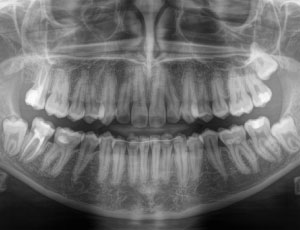

歯の中には神経や血管が通った細い管があり、根管と呼ばれます。

外傷や虫歯などで歯の中の神経にも影響がある場合に行うのが歯内療法です。

虫歯を放置してしまい歯の中の神経に到達してしまうと痛みが出たりしみるようになります。この場合は細菌に感染した歯髄を除去する「抜髄」という治療を行います。

虫歯が進行したり、歯を強く打ち付けた場合、歯の中の神経が死んでしまうことがあります。神経は死んでしまうとそのまま歯の中で腐り歯の根の先まで細菌に感染すると噛んだときに痛むようになります。

歯の神経が死んでしまい、空洞ができた部分で細菌が繁殖すると膿の袋を作るようになります。初期症状はありませんが、身体の抵抗力が落ちた際に痛みが出たり、蓄膿症の原因になったりします。

歯の根の先に膿がたまると、白いニキビのようなできものになる場合があります。膿を出し切ることで一時的に改善しますが、また膿がたまると再発を繰り返します。膿は口臭の原因になることもあります。